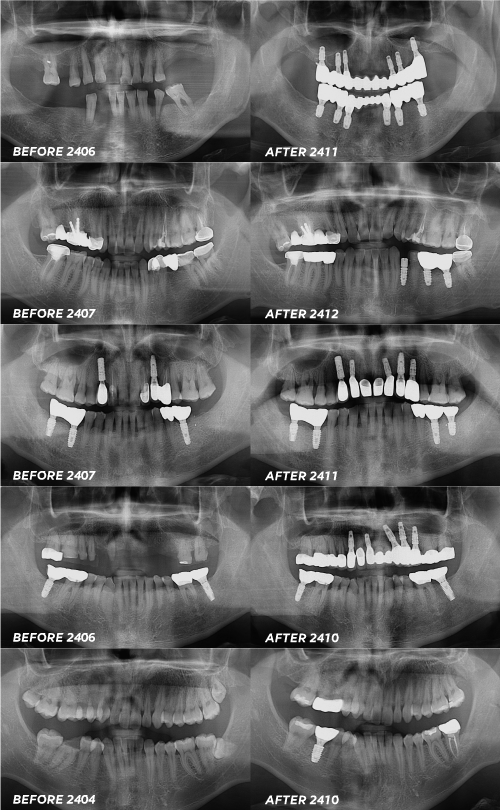

임플란트는 한 가지 구성요소가 아닌

여러 가지 구성요소로 이루어져 있는데

그중에서도 픽스처라고 불리는 인공 치근

표면 처리 방식에 따라 등급이 나뉘어요.

이 인공치근이 등급이 나뉠 만큼 중요한 부분인데요.

잇몸 안쪽의 뼈 속에 심어질 부분이며

치아 뿌리의 역할을 해주는 부분이 되는 것이기 때문에

그만큼 중요한 역할을 하는 부위라고

말할 수밖에 없는 부분이에요.

이 픽스처에 대한 등급에 대해서

하나씩 찬찬히 살펴보도록 할게요.

픽스처(인공뿌리) 등급

등급은 총 5가지로 나뉘어요.

SA, CA, HA, BA, SOI

기본적으로 베이직한 제품은 SA로

특별하지 않은 경우의 임플란트 케이스에

보편적으로 사용하는 제품입니다.

잇몸 뼈 상태가 어느 정도는 보통에서

좋은 경우에만 진행한다고 볼 수 있어요.

또한 가장 기본적으로 많이 찾으시는 이유가

보험 임플란트의 재료로 많이 사용되기 때문입니다.